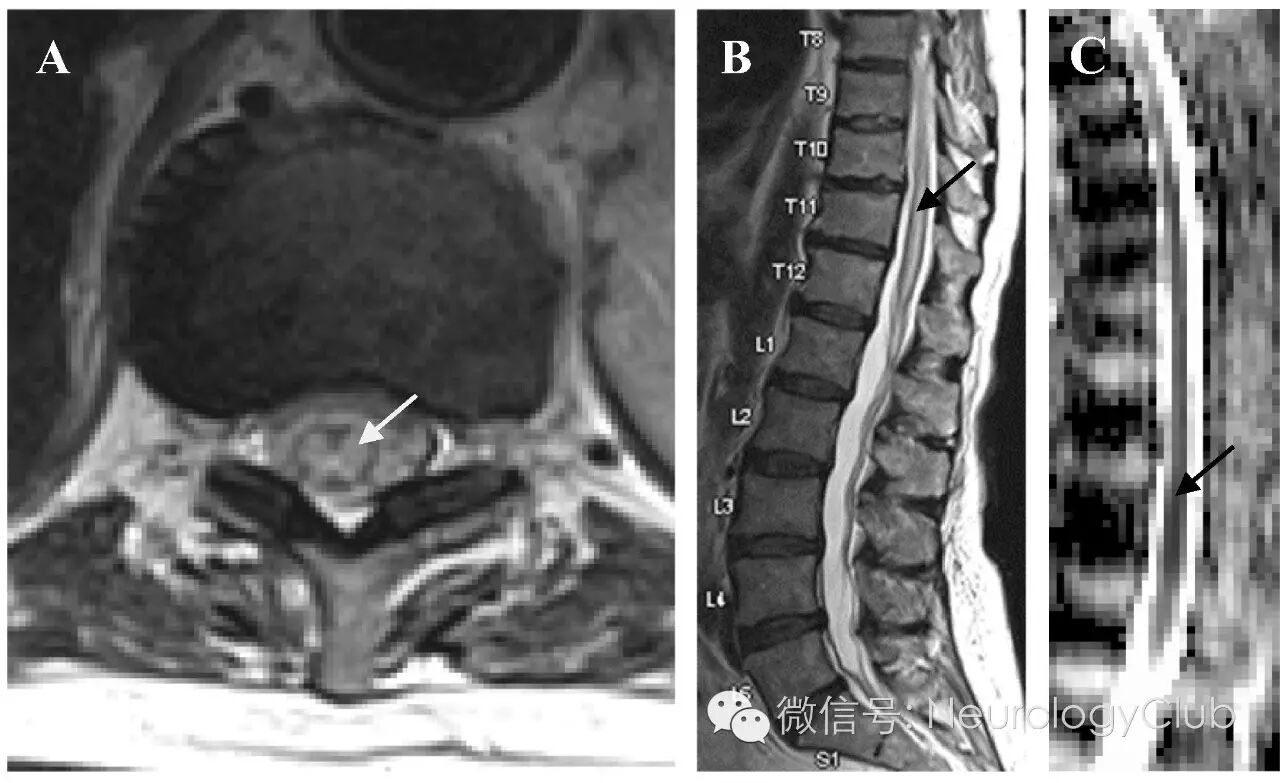

(图1:横断面[A]和矢状位[B]T2WI以及矢状位ADC[C]可见脊髓病灶[箭])

脊髓梗死的典型MRI特征为中央T2高信号,不伴有明显的脊髓扩张或强化。如果条件允许的话,DWI上可见对应的弥散受限,与急性脑梗死相同。本例患者的MRI改变明显,横断面T2WI上可见H形高信号病灶(图1A),局限于脊髓灰质,符合对缺氧最敏感的神经元核周体分布区。明显的脊髓弥漫ADC低信号与DWI上高信号区域基本一致,证实病灶弥散受限,提示为急性缺血性过程(图1B-C,图2B)。CT主动脉造影(图2A)证实严重的动脉粥样硬化伴钙化,贯穿主动脉和其主要的腹部分支,这正是该年龄人群脊髓梗死的常见潜在原因。